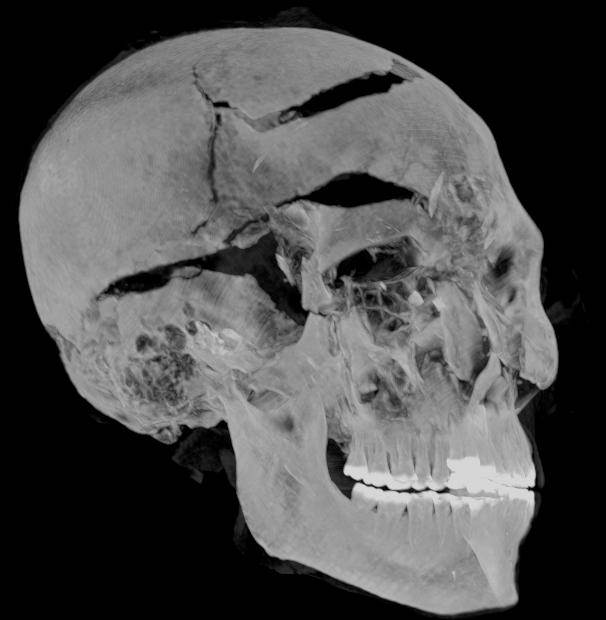

في بحثهما، قدم الباحثان المصريان زاهي حواس وسحر سليم تفسيرًا جديدًا للأحداث قبل وبعد وفاة الملك سقنن رع، استنادًا إلى صور الأشعة المقطعية ثنائية وثلاثية الأبعاد والتي تم تركيبها بواسطة تقنيات الكمبيوتر المتطورة، فيظهر تشوه الذراعين أنه يبدو أنه قد تم بالفعل أسر سقنن رع-تاعا الثاني في ساحة المعركة، وقيدت يديه خلف ظهره، مما منعه من صد الهجوم الشرس عن وجهه.

ولقد كشف التصوير المقطعي لمومياء سقنن رع تاعا الثاني عن تفاصيل دقيقة لإصابات الرأس بما في ذلك جروح لم يتم اكتشافها في الفحوصات السابقة حيث أخفاها المحنطون بمهارة. واشتمل البحث دراسة أسلحة مختلفة للهكسوس محفوظة بالمتحف المصري بالقاهرة وشملت فأس وحربه وعدة خناجر.

وأكدا سحر سليم وزاهي حواس تطابق هذه الأسلحة مع جروح سقنن رع تاعا الثاني، فتشير النتائج أنه قتل من قبل مهاجمين متعددين من الهكسوس أجهزوا عليه من زوايا مختلفة وبأسلحة مختلفة فكان قتل سقنن رع على الأحرى إعداما احتفاليا.

كما حددت دراسة التصوير المقطعي أن سقنن رع تاعا الثاني كان يبلغ من العمر قرابة الأربعين عامًا عند وفاته ، بناءً على شكل العظام (مثل مفصل ارتفاق العانه) والذي تم الكشف عنه في الصور ، مما يوفر التقدير الأكثر دقة حتى الآن.

بالإضافة إلى ذلك، كشفت دراسة التصوير المقطعي المحوسب عن تفاصيل مهمة حول تحنيط جسد سقنن رع تاعا الثاني، على سبيل المثال ، استخدم المحنطون طريقة متطورة لإخفاء جروح رأس الملك تحت طبقة من مادة التحنيط التي تعمل بشكل مشابه للحشوات المستخدمة في الجراحة التجميلية الحديثة، وهذا يعني أن التحنيط تم في ورشة تحنيط بالفعل وليس في مكان غير معد ، كما تم تفسيره سابقًا.